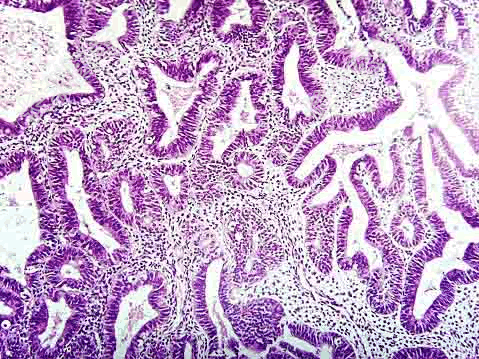

- 单项选择题女性,40岁, 月经量多不规律2月余,诊刮子宫内膜, 显微镜下见腺体增生,与间质比> 3:1, 腺上皮部分出现假复层,核无明显异型(如图), 应诊断为 ( )

A、子宫内膜单纯性增生

B、子宫内膜复杂性增生

C、子宫内膜单纯性增生伴非典型增生

D、子宫内膜复杂性增生伴非典型增生

E、子宫内膜腺癌